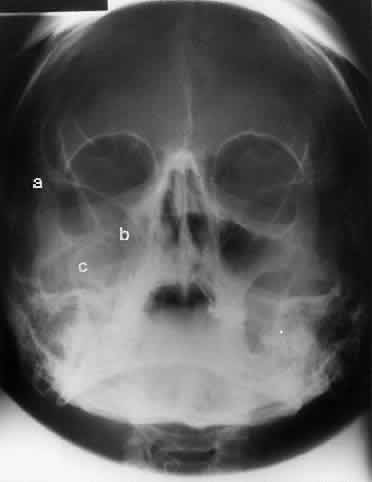

WATERS PROJECTION

In an attempt to improve the visualization of the maxillary and ethmoid sinuses, in 1915 Waters and Waldron7 described a radiographic projection (Fig. 2) that eliminated the overlapping shadows of the dense petrous ridge of the temporal bone. Waters projection is created by placing the chin of the patient on the x-ray cassette with the canthomeatal line (the line that connects the lateral canthus and the external auditory meatus) at 37 degrees to 45 degrees.5,6 This orientation is accomplished if the nose of the patient is approximately 0.5 to 1.5 cm above the x-ray plate.7,8 A mnemonic is—the patient raises the chin up to sip water.

Fig. 2. A. Schematic showing positioning for a Waters projection. (CM, canthomeatal line; CR, central ray) B. Radiograph of a Waters projection. The petrous ridge lies below the maxillary sinus. (a, frontal sinus; b, medial orbital wall; c, innominate line; d, inferior orbital rim; e, orbital floor; f, maxillary antrum; g, superior orbital fissure; h, zygomatic-frontal suture; i, zygomatic arch) (A; Rao VM, Gonzalez CF: Plain film radiography and polytomography of the orbit. In Gonzalez CF, Becker MH, Flanagan JC [eds]: Diagnostic Imaging in Ophthalmology, pp 1–7. New York, Springer Verlag, 1986)

Waters view provides the best image of the maxillary antrum and good images of the orbital rim, orbital floor, zygomatic bones and arches, lesser wing of the sphenoid, and infraorbital foramen. This view is useful to the clinician in orbital floor fracture assessment because of the clear image of the orbital floor and the underlying maxillary sinus. The floor of the orbit should form a continuous radiographic line with the lateral wall of the orbit. Confusion can occur regarding the location of the orbital floor and its relationship to the orbital rim. The orbital floor is located inferior to the orbital rim not in the same plane, because of the orientation of the patient's head in Waters projection. A soft tissue density in the roof of the maxillary sinus or opacification of the floor of the sinus suggests an orbital floor disruption.